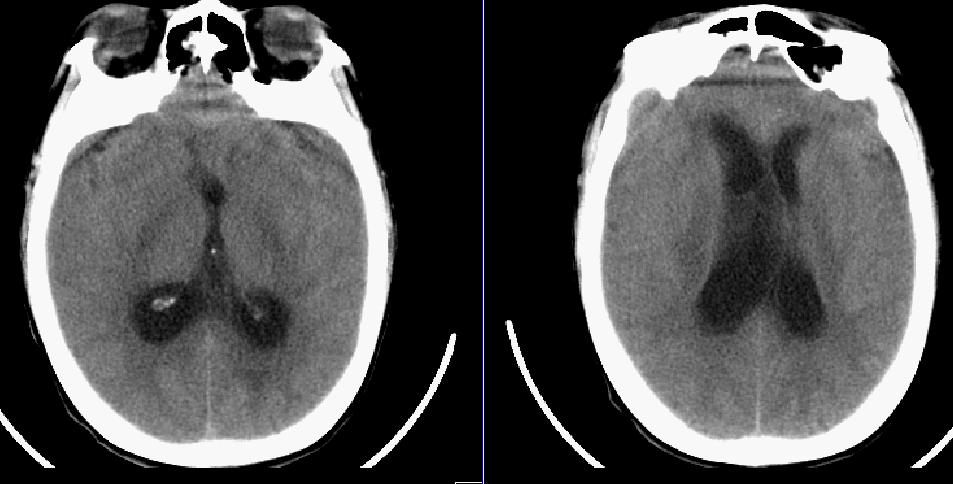

患者,女,32岁,因胆囊结石入院,手术非常成功,准备出院,突然却昏迷不醒,ct检查发现。。。。。

脑积水,脑肿胀。不知小脑及脑干如何,请上传

弥漫性脑梗塞致脑水肿、脑积水。(桥中脑多发低密度区)

脑水肿;梗阻性脑积水。

临床上考虑的结核性脑膜炎,现在正在查脑脊液。